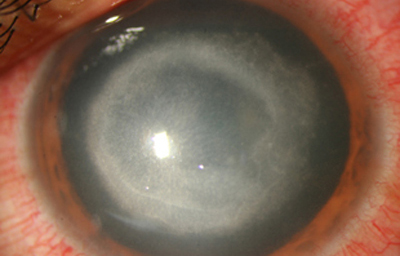

Superficie corneal irregular y grisácea, (Fig. 1, 2) con opácidades granulares en parche y formación de líneas epiteliales elevadas de aspecto granular (Fig. 3), que pueden arborizar dando imágenes de pseudodendritas. Opacidades superficiales satélites. (Figura 4) Inyección ciliar. Ulceración epitelial variante. (Figura 5).

Fig. 1 Síntomas de 15 días evolución